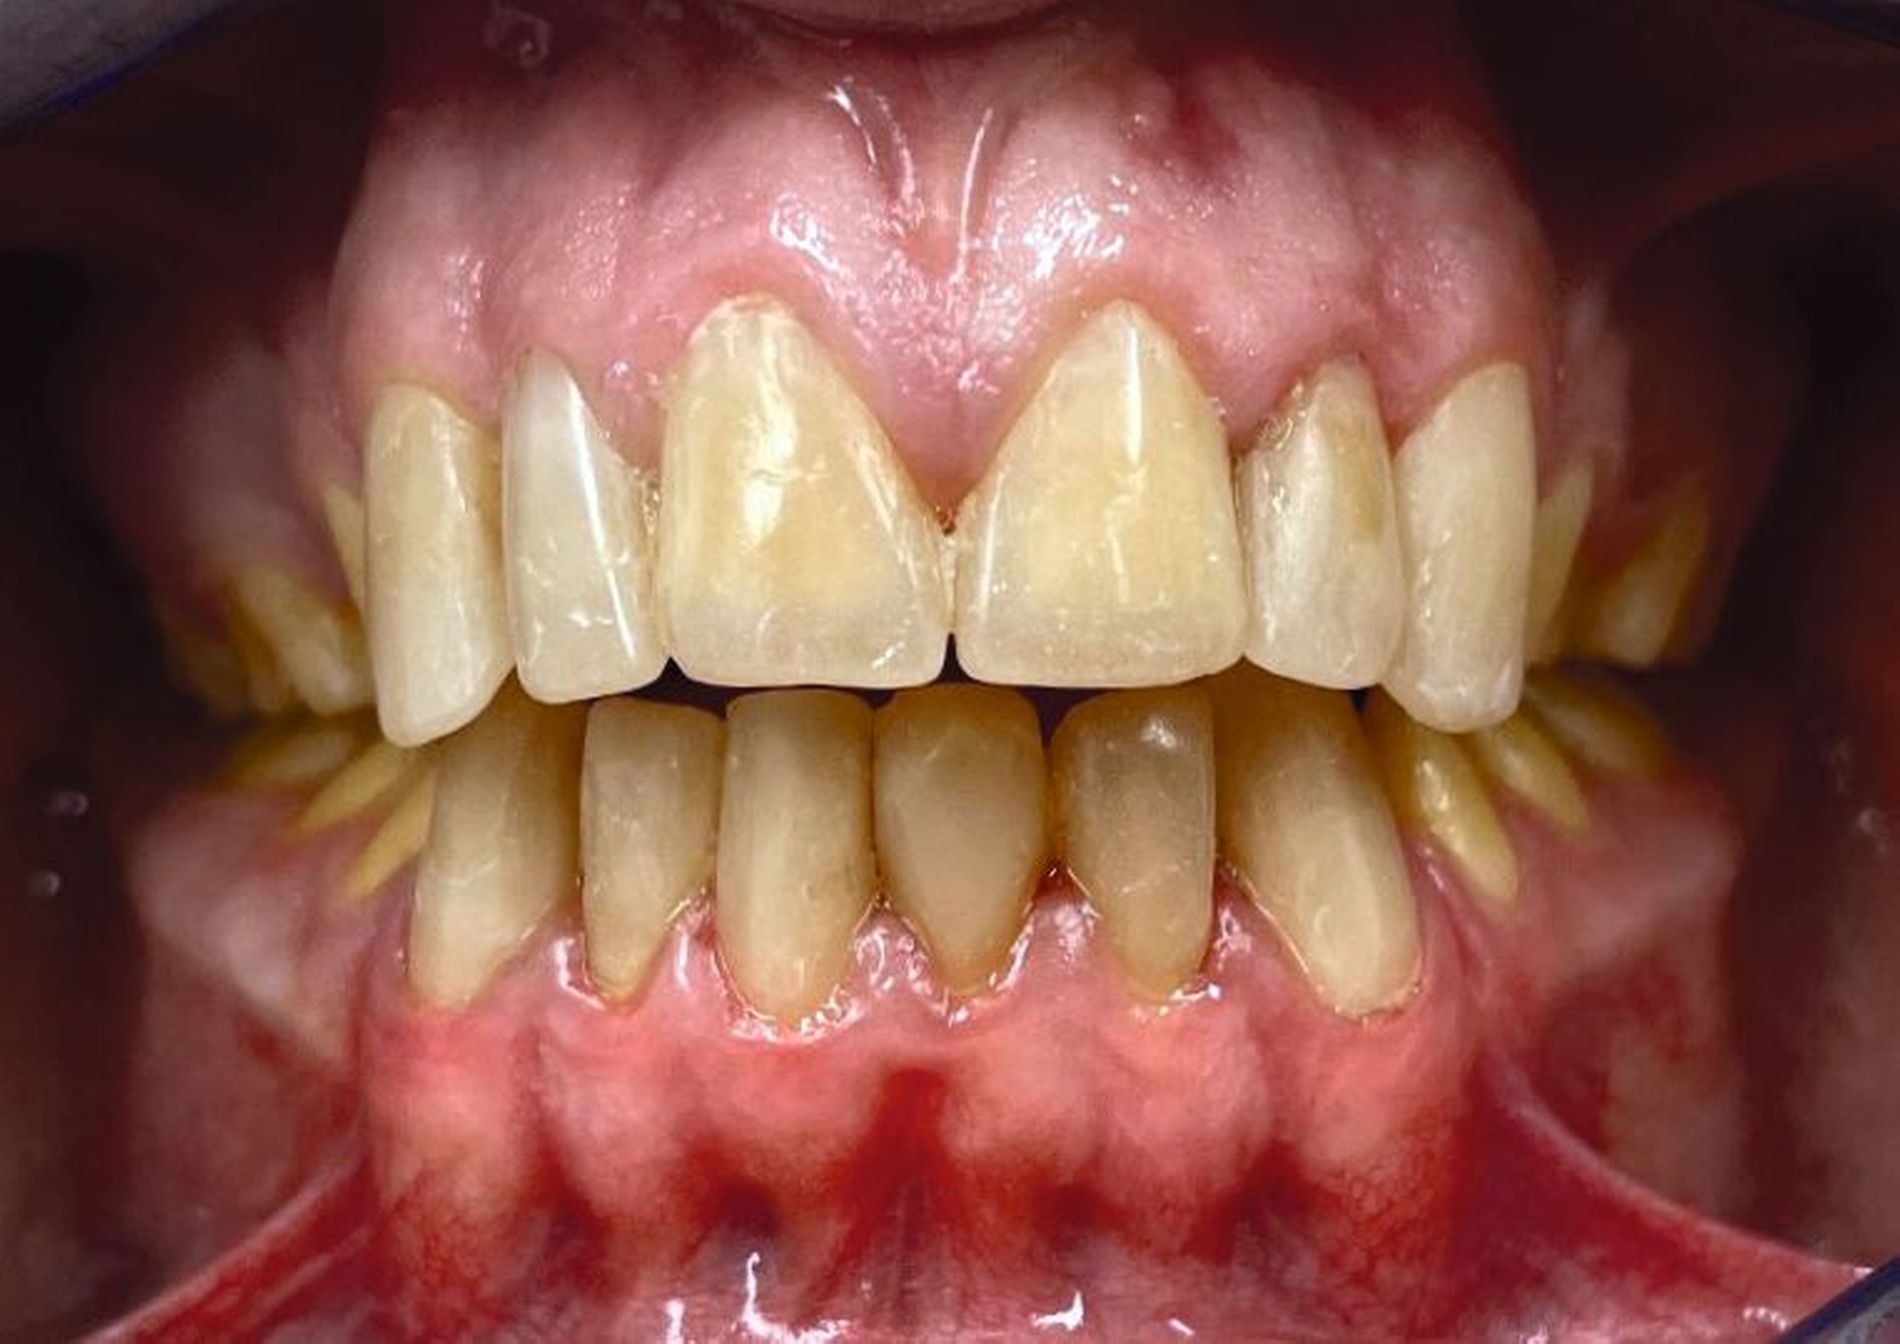

Klinisch zeigte sich ein kariöses Wechselgebiss mit generalisierten Verfärbungen und rauer Schmelzoberfläche. Mehrere Milch- und bleibende Zähne wiesen aktive kariöse Läsionen auf. Zahn 64 war zusätzlich druckdolent und gelockert, mit einer vestibulären Schwellung der Gingiva. Zudem bestanden eine Mittellinienabweichung, ein Overbite von vier Millimetern und ein Overjet von elf Millimetern (Abbildung 1). Extraoral fiel ein fliehendes Kinn mit inkomplettem Lippenschluss und hyperaktivem Musculus mentalis auf. Röntgenologisch waren alle Zähne angelegt, der Zahnschmelz zeigte jedoch eine reduzierte Opazität (Abbildung 2). Eine genetische Abklärung wurde von den Erziehungsberechtigten aus ethischen Gründen abgelehnt.

Klinisch zeigten sich ein nicht-kariöses Wechselgebiss mit generalisierter Schmelzhypoplasie an allen Zähnen sowie eine insuffiziente Mundhygiene. Zusätzlich bestanden eine fehlende Mittellinienübereinstimmung, ein Overbite von minus vier Millimetern und ein Overjet von sechs Millimetern (Abbildung 5), die sich phonetisch in einem interdentalen Sigmatismus äußerten. Röntgenologisch waren alle Zähne angelegt, jedoch war der Zahnschmelz stark reduziert oder vollständig fehlend (Abbildung 6).